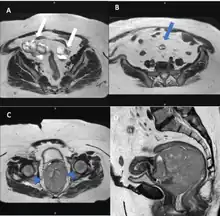

Magnetic resonance imaging

Although magnetic resonance (MRI) scans are not commonly employed for ovarian cancer detection, the majority of ultrasound-detected ovarian masses are usually benign. The combined approach of ultrasound with Doppler, along with the selective use of contrast-enhanced MRI, proves to be an efficient diagnostic method for identifying benign adnexal masses with distinctive features, including functional masses, dermoid, endometrioma, fibroma, pedunculated fibroid, hydrosalpinx, and peritoneal inclusion cysts.[19] This integrated diagnostic strategy is effective in preventing unnecessary surgical intervention. Additionally, the use of MRI contributes to a decrease in false-positive diagnoses, ultimately reducing the overall number of unnecessary surgical procedures related to ovarian masses.